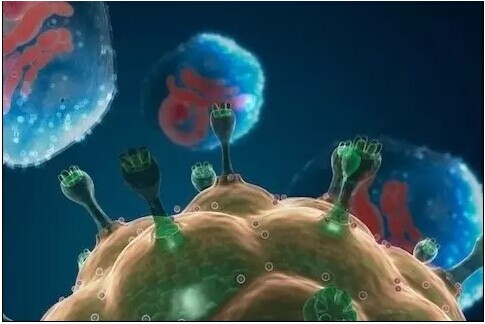

细胞